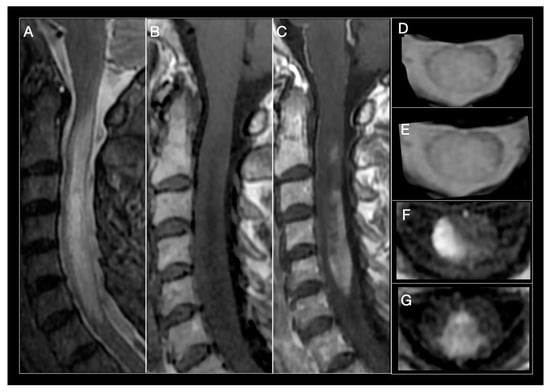

| Spinal cord MRI | Small, peripheral, posterolateral lesions Less than 3 segments Gadolinium enhancement during acute phase | LETM or multiple short segment myelitis Edematous lesions and gadolinium enhancement in acute phase | Central LETM Edematous Necrosis or cavitation Gadolinium enhancement in acute phase | LETM or short myelitis, frequent conus medullaris involvement Linear gadolinium enhancement of the ependymal canal | LETM Central lesions |